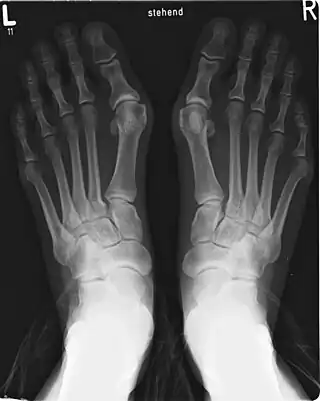

Radiografías que permiten comparar las desviaciones del dedo gordo en hallux valgus y hallux varus.

• Hallux valgus, o juanetes: Desviación del primer dedo del pie fuera de la línea media, acompañado además de una protuberancia (exostosis) en la articulación metatarsofalángica, constituyendo la patología más frecuente de la articulación, con una prevalencia del 28,4 % de la población general.[100][101] Existirían dos formas de hallux valgus, uno congénito, de aparición en la infancia y con una prevalencia similar entre sexos, y otra principalmente adquirida, que en su gran mayoría afecta al pie egipcio, con mayor prevalencia en mujeres, y cuyas causas sería el calzado inadecuado o brotes reumáticos (artritis reumatoide).[89] También se señala como causa traumatismos, pie plano, trastornos neuromusculares, trastornos de tejido blando o inestabilidad de la articulación metatarsofalángica.[102]

• Hallux varus: deformidad de la articulación del dedo gordo del pie que provoca la desviación medial (interna o hacia el lado tibial) del dedo gordo partiendo del primer metatarsiano. El dedo gordo se mueve habitualmente en el plano transversal. En este sentido se trataría del defecto contrario al hallux valgus.[103]